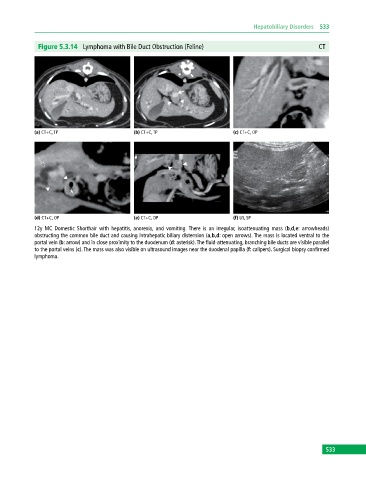

Figure 5.3.14 Lymphoma with Bile Duct Obstruction (Feline) CT

(a) CT+C, TP (b) CT+C, TP (c) CT+C, OP

(d) CT+C, OP (e) CT+C, DP (f) US, SP

12y MC Domestic Shorthair with hepatitis, anorexia, and vomiting. There is an irregular, isoattenuating mass (b,d,e: arrowheads)

obstructing the common bile duct and causing intrahepatic biliary distension (a,b,d: open arrows). The mass is located ventral to the

portal vein (b: arrow) and in close proximity to the duodenum (d: asterisk). The fluid‐attenuating, branching bile ducts are visible parallel

to the portal veins (c). The mass was also visible on ultrasound images near the duodenal papilla (f: calipers). Surgical biopsy confirmed

lymphoma.